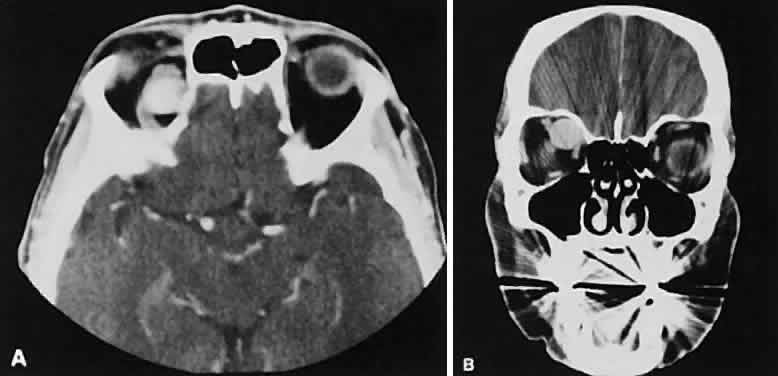

The edema and inflammatory infiltrate that accompany infections are indistinguishable from that associated with orbital inflammations. The presence of sinus disease, however, is a more constant feature with infections, because the sinus represents the infectious nidus in most cases (Fig. 9). In addition to the frequent appearance of sinus disease, the adjacent EOM is invariably enlarged. Less often, orbital infections may be transmitted through the blood, related to a retained foreign body, or spread from the lids. Chandler and colleagues47 classified orbital infections into five groups. Group 1 (preseptal cellulitis) represents inflammatory edema and reflects congestion of venous outflow. Group 2 has actual orbital infiltration/edema with mass effects and functional deficits. Group 3 includes patients with subperiosteal abscesses. Most of these dome-shaped subperiosteal abscesses are located along the medial wall. Group 4 includes patients with orbital abscesses who may display a ring-enhancing lesion with mass effect. Group 5 represents intracranial extension of the inflammation into the cavernous sinus or sinuses, which appear engorged and opacified.

Fig. 9. Orbital cellulitis. A. Axial view shows a subperiosteal soft-tissue mass displacing the medial rectus muscle. The ethmoidal sinus is opacified secondary to inflammatory disease, which invariably precedes the orbital inflammation. B. Coronal view further shows the subperiosteal and ethmoidal sinus inflammation. Inflammation changes also are seen in each maxillary sinus.